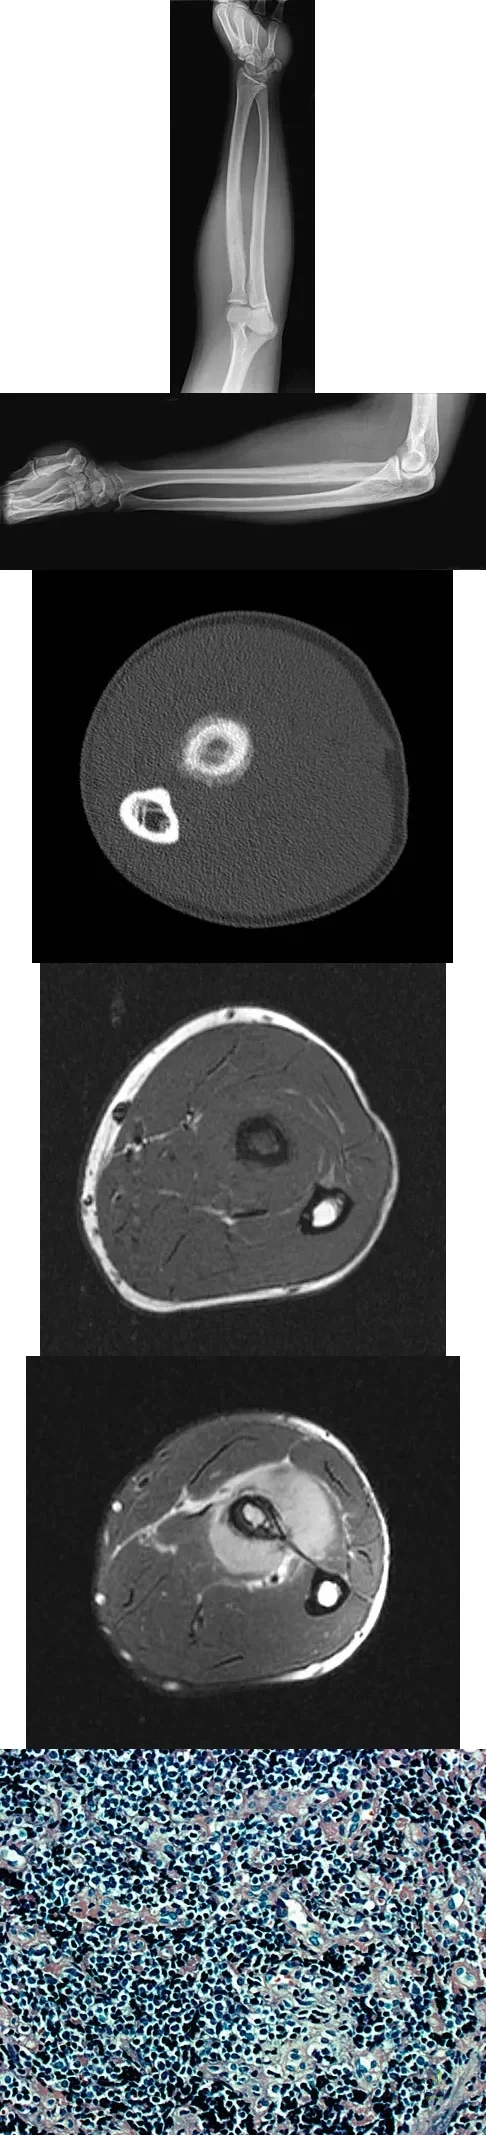

Question 34

A 19-year-old man has had pain and swelling in his left forearm for the past 8 months. Laboratory studies show a mildly elevated WBC count and erythrocyte sedimentation rate. Radiographs are shown in Figures 58a and 58b, a CT scan is shown in Figure 58c, and T1- and T2-weighted MRI scans are shown in Figures 58d and 58e, respectively. A biopsy specimen is shown in Figure 58f. Immunohistochemistry demonstrates that the lesion is negative for leukocyte common antigen (CD34). What is the most common cytogenetic translocation associated with this lesion?

Explanation